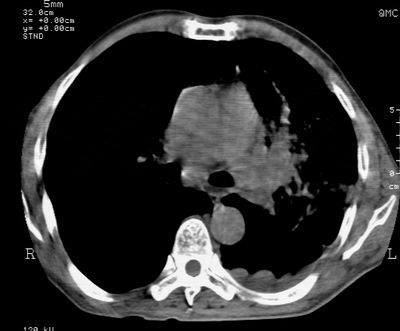

标题: CT24000:M65,胸痛,胸闷月余,既往慢支,肺气肿,肺心病 [打印本页]

标题: CT24000:M65,胸痛,胸闷月余,既往慢支,肺气肿,肺心病

1左侧胸腔积液

左肺门肿块,相应支气管闭塞,左肺上叶、舌叶大片及散在高密度影,部分呈不张改变,两肺纹粗乱,左侧胸腔积液。考虑左侧中央型肺癌伴阻塞性改变。

左肺门见巨大软组织肿块影,直径约--,境界清,左上肺叶支气管变窄,左上肺舌叶见大片状密实影,余肺纹理增多、紊乱、纤细、部分网格状,两肺透亮度增高,纵隔内见增大多发淋巴结影,心影略左偏,左侧少量胸腔积液。

左侧中央型肺癌伴左上肺舌叶不张、纵隔淋巴结转移,左侧少量胸腔积液。